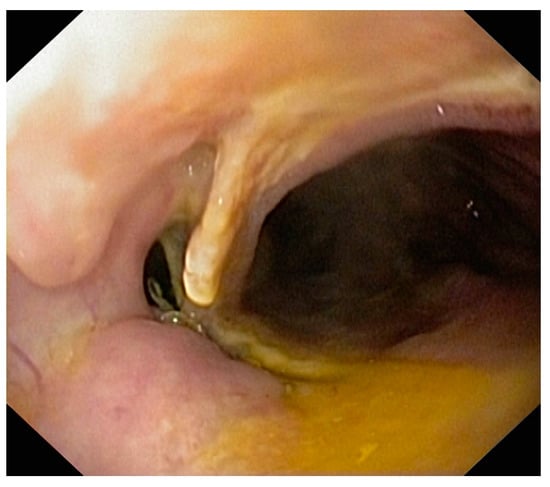

Figure 2.

Persistence of the fistula of esogastric anastomosis after stent extraction at 3 weeks.